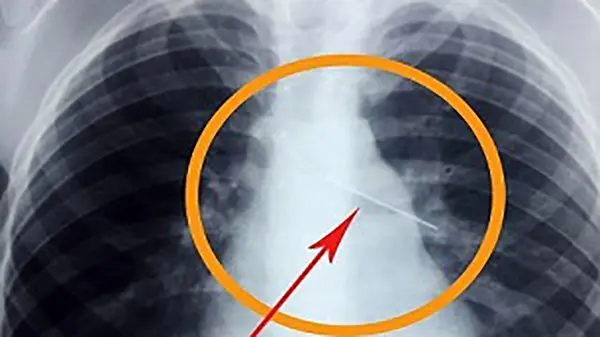

سوزن 4 سانتی در کبد نوزاد 11 ماهه جاخوش کرده بود

رکنا: سوزن 4 سانتی که با جاخوش کردن در کبد نوزاد 11 ماهه ای جان وی را به خطر انداخته بود با جراحی ویژه ای در قشم خارج شد.

تیم پزشکى اتاق عمل بیمارستان پیامبر اعظم (ص) شهر قشم پس از یک عمل جراحی 2 ساعته، جان نوزاد قشمى را از مرگ حتمى نجات دادند.

تیم پزشکی بیمارستان پیامبر اعظم (ص) شهر قشم، سوزن 4 سانتی را از کبد و شکم کودکی 11 ماهه خارج کردند.

این نوزاد زمانی که بر روى فرش خانه در حال بازى کردن بوده است، یک سوزن 4 سانتى را بلعیده است.

بعد از معاینههاى پزشکى و آزمایشات مختلف، سوزن از بدن این نوزاد خارج شد. برای ورود به کانال تلگرام ما کلیک کنید.